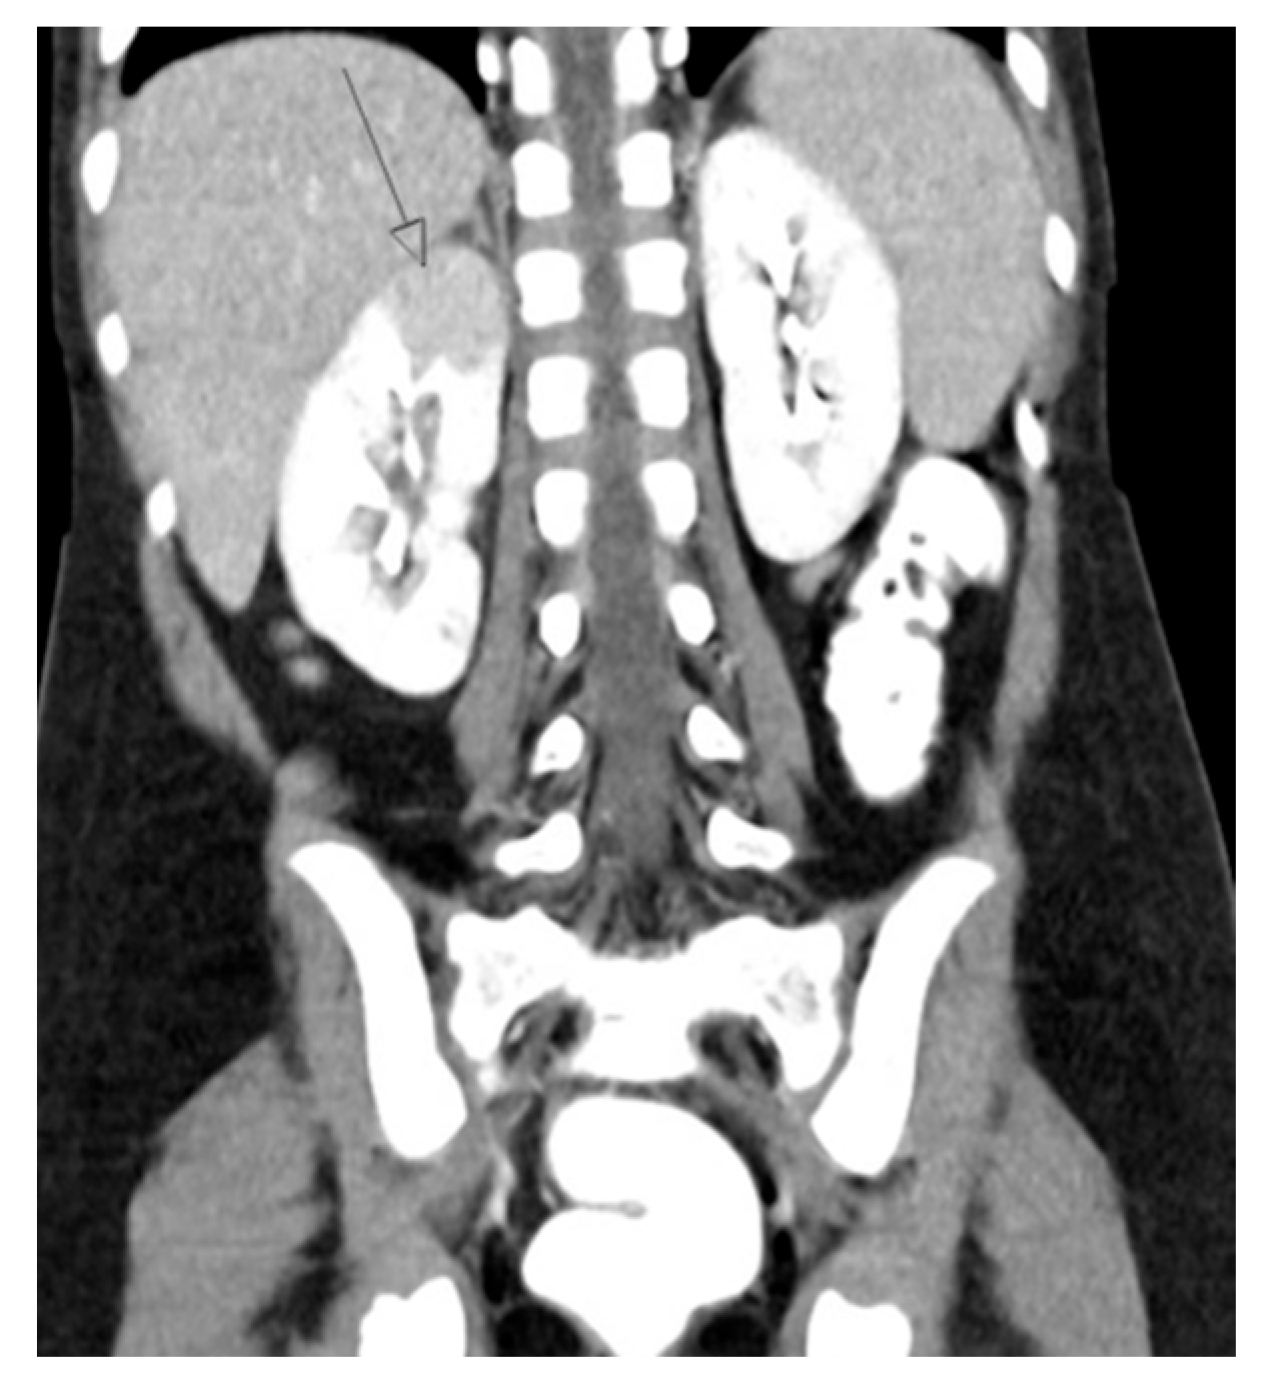

5. Computed Tomography (CT)

5.1. Technique

5.2. Application

20. Nephrolithiasis